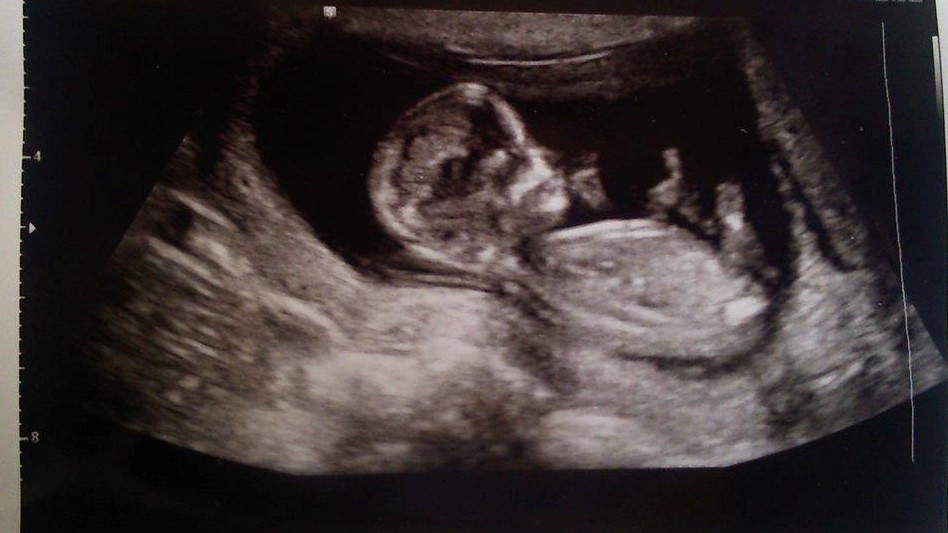

Please. Any guesses on a boy or girl please? Skull/Nub Theory?

Are there any signs at all in my scan photos about whether I'm carrying a boy or a girl?

I know they aren't the clearest photos, but they're the only ones I have.

12 weeks

Attachment 36255